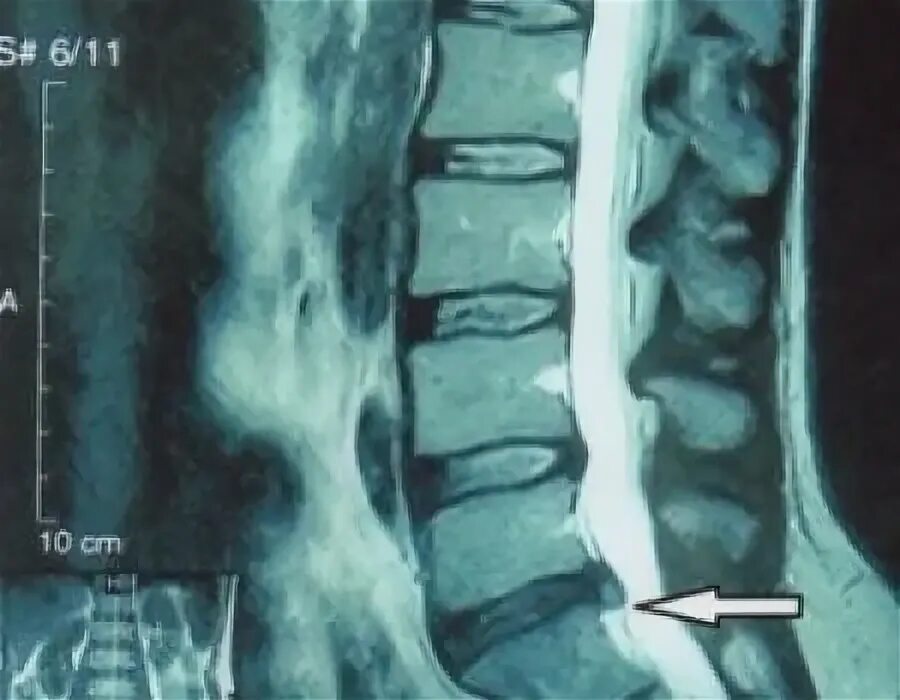

Можно ли бегать при грыже поясничного отдела